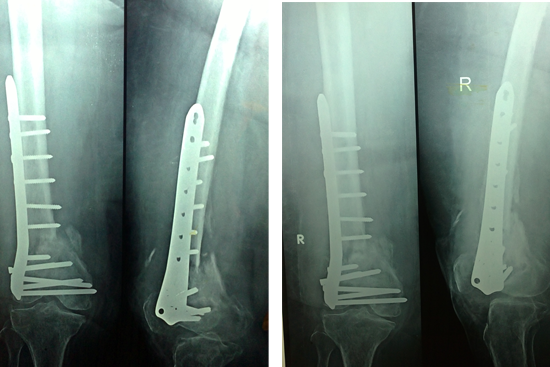

Non Union Femur

Case 1